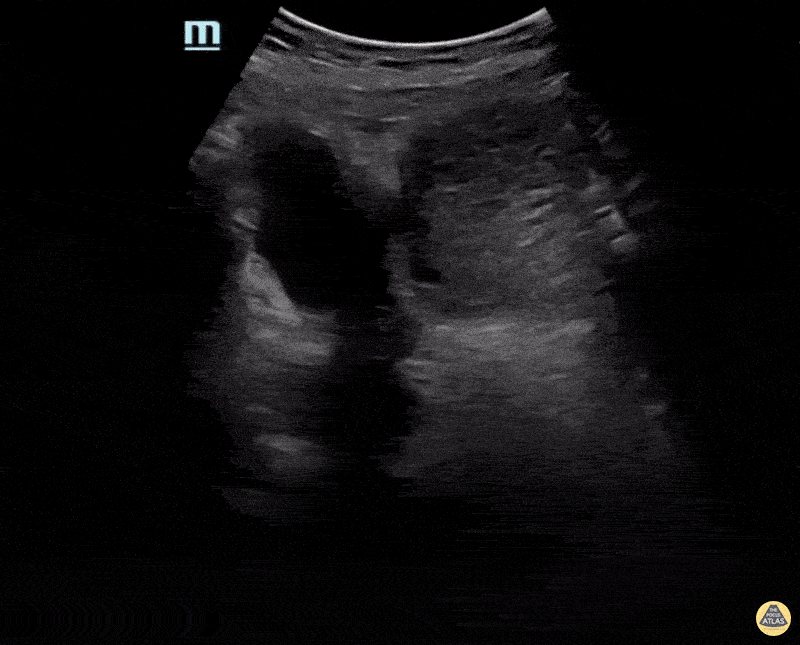

OB/Gyn - Partial Molar Pregnancy Transverse

Patient was having significant nausea and vomiting and went to her local ER. While there her beta HCG was much higher than expected at her gestational age. Ultrasound shows a large amount of heterogeneous material with possible gestational sac. Confirmed after D&C. Michael Bernard, DO